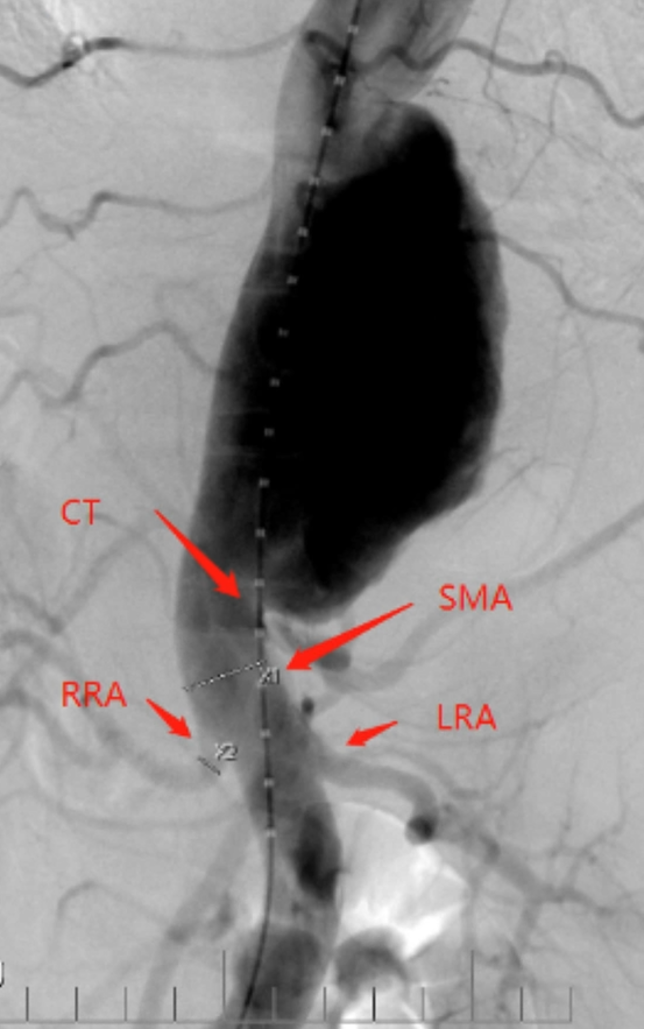

病例1 两开窗:

病例2 四开窗:

手术时间382分钟

造影剂用量320ml